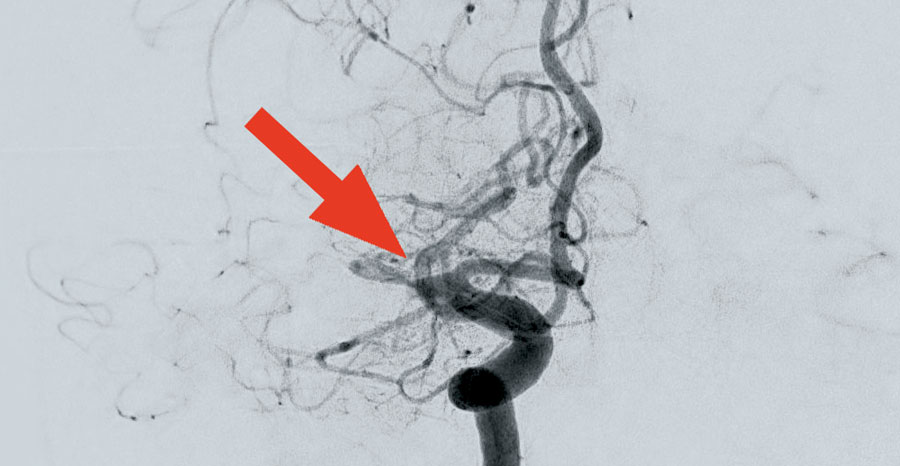

Wie kann man sich so einen Eingriff mittels Angiografie vorstellen? Vereinfacht gesagt: Mit Kathetern wird über die rechte Leiste der Weg über die Beckenarterien und die Aorta bis zum Aortenbogen und von dort über die Hals- oder Wirbelsäulenschlagader bis in die Hirnbasisarterien gegangen. Mit dem Röntgen-Durchleuchtungsgerät – für Spezialisten: eine biplane Flachdetektor 3D-Rotationsangiografie Azurion – lässt sich das bestens am großen Monitor über dem Behandlungstisch verfolgen und steuern. Ist das Blutgerinnsel erreicht, wird darüber ein sogenannter Stent-Retriever eingebracht. Dieser soll sich mit seinen Maschen in das Blutgerinnsel „hineinfressen“. Das „gefangene“ Blutgerinnsel wird dann mit dem Stent-Retriever zurückgezogen. Über einen zusätzlichen Katheter wird ein Sog erzeugt, der die gelösten Blutgerinnselanteile aus der Arterie „heraussaugt“.

Voraussetzung für die Behandlung eines Schlaganfalls ist, dass es sich nicht um einen „manifesten Infarkt“ handelt. Sprich, dass also bestimmte Regionen des Gehirns nicht schon zu lange unterversorgt waren. Einer der ersten Fälle für Dr. Johannes Waidelich war gleich ein eher ungewöhnlicher: 97 Jahre alt war die Patientin, allerdings als Selbstversorgerin und ohne relevante Vorerkrankungen noch sehr gut aufgestellt war. Schon 40 Minuten nach Eintreffen der Dame konnte Dr. Waidelich mit der Behandlung beginnen und erfolgreich ein Blutgerinnsel aus der mittleren Hirnschlagader entfernen.